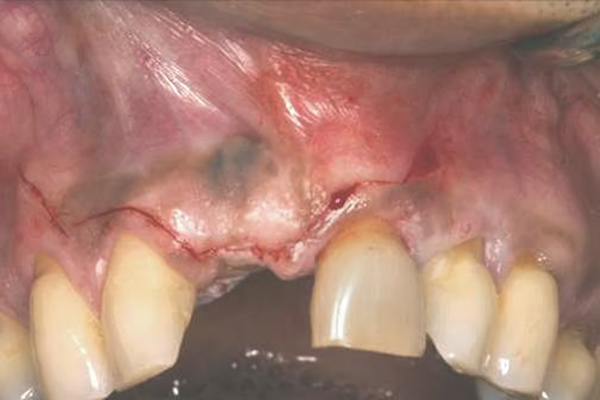

In the esthetic zone it is preferable to avoid elevating papillae because flap elevation may induce recession and create unesthetic black triangles.4 If a flap is necessary to perform a procedure in an edentate area when adjacent teeth are present, the following technique can be used to circumvent blunting papillae. Make a horizontal incision along the midcrestal or palatal aspect of the ridge and terminate the incision 1 mm from the adjacent teeth (Figure 1). The incision is created palatally if it is desired to transpose keratinized tissue to the buccal. From the horizontal incision, create bilateral buccal vertical releasing incisions that extend obliquely at an angle (Figure 2). The vertical incisions can also be extended palatally (for access), but this is not always necessary (Figure 3). Preserved papillae contain gingival supracrestal fibers that subsequently help maintain papillary height (Figure 4). The distance the incision is extended vertically on the buccal is dictated by the task to be accomplished (eg, implant insertion only requires short vertical incisions, while bone grafting needs longer incisions) (Figure 5 and Figure 6). At the end of the surgical procedure, the severed papillary segments are sutured to their retained counterparts (Figure 7 and Figure 8). Figure 1 through Figure 8 demonstrate a submerged implant protocol.

Fig 17. Vertical and horizontal incisions were sutured to attain primary closure.

Fig 20. Papillae-sparing incisions were developed both horizontally and vertically. The pedicle flap was elevated, exposing a thin ridge.

Fig 21. A dental implant was placed at the site of tooth No. 10. A defective buccal ridge was noted.

Fig 22. A straight healing abutment was attached to the implant. The barrier (held back with the periosteal elevator) was placed before the bone graft insertion.

Fig 23. The healing abutment in place. Horizontal and vertical incisions were sutured.